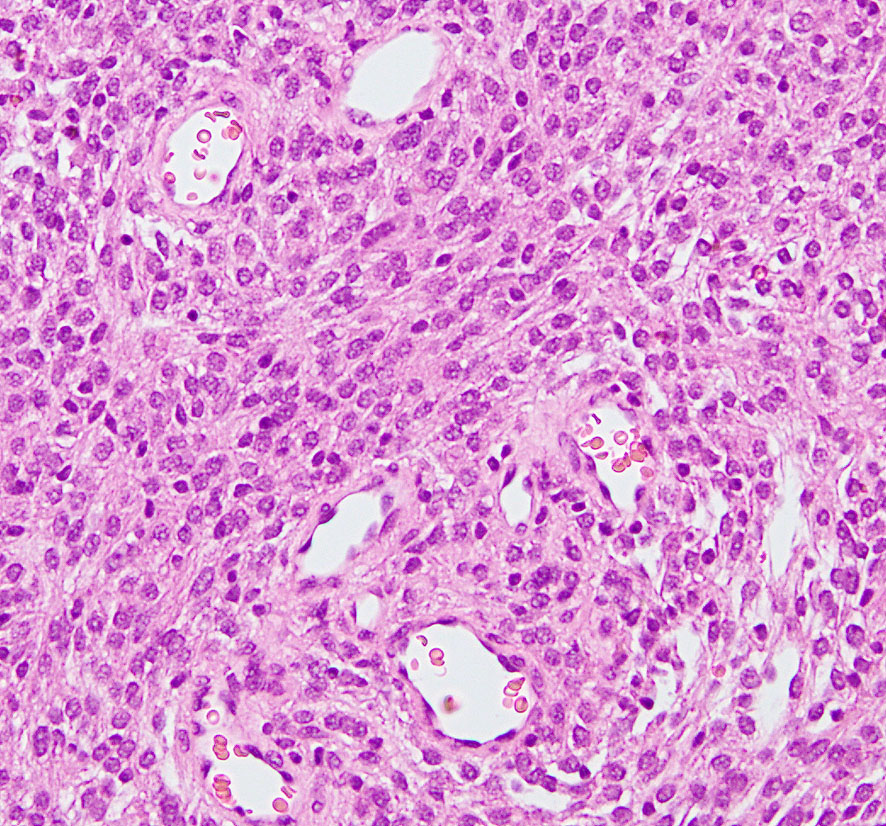

angiomatous meningioma WHO grade 1 血管腫様髄膜腫

術前検査ではまるで膠芽腫のような画像です。でも,開けてみれば髄膜腫ということはすぐにわかる肉眼所見です。硬膜の至る所から腫瘍血管が流入して出血性腫瘍です。

多数の小血管から構成される組織像です。右のvimentin染色は陽性です。

核小体明瞭な大小不同な類円形核からなる細胞境界が不明瞭な腫瘍細胞がみられ,ヘモジデリン貪食マクロファージも認められます。MIB-1染色率は2-3%でグレード1です。